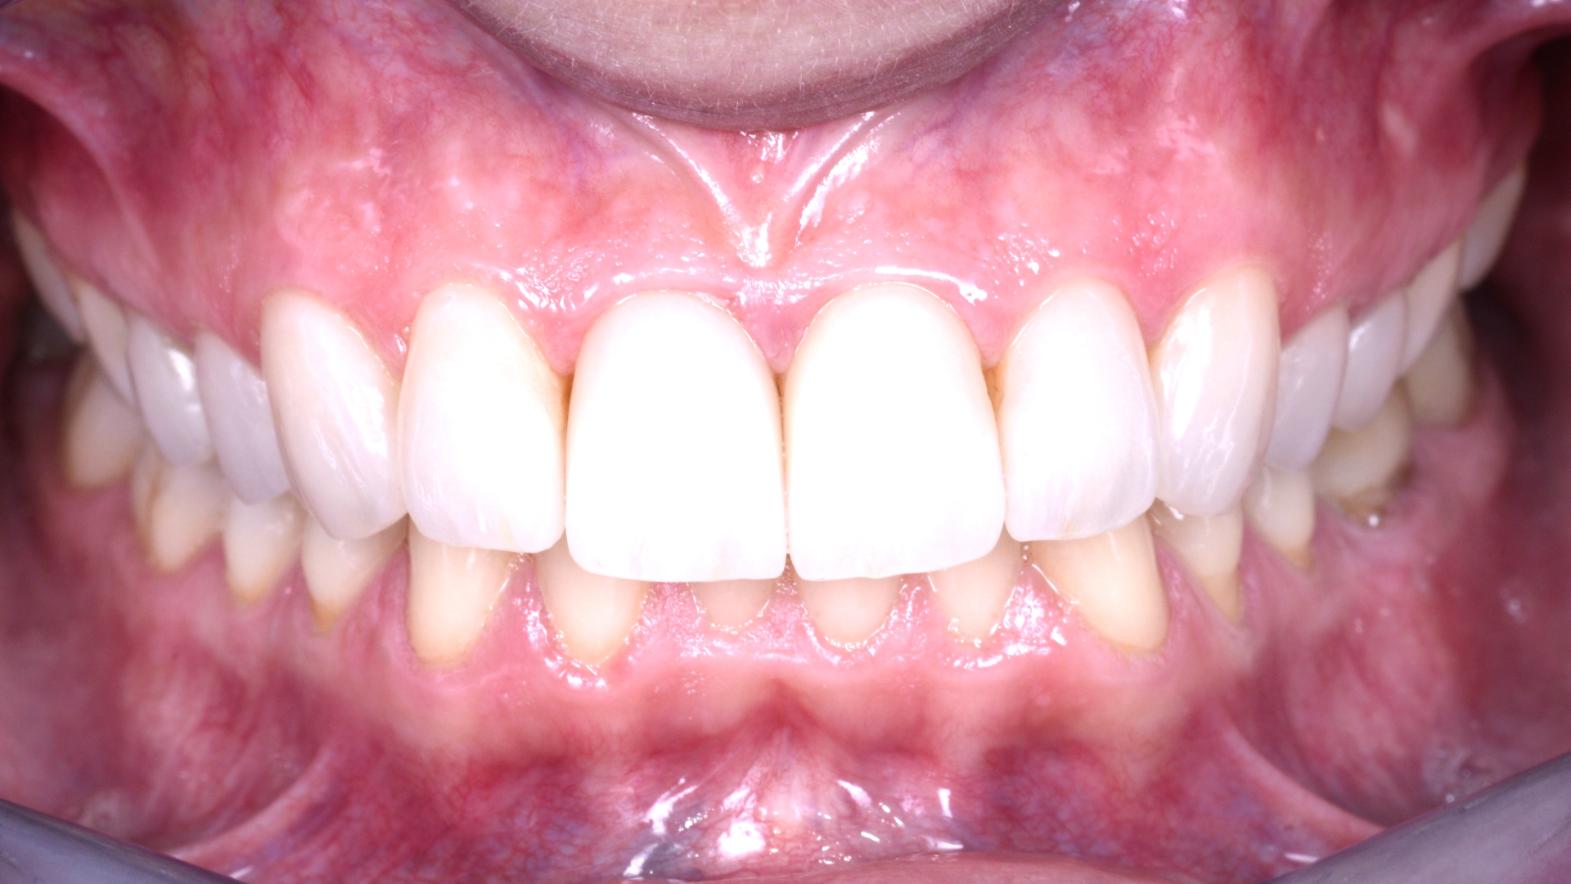

Dopo il trattamento